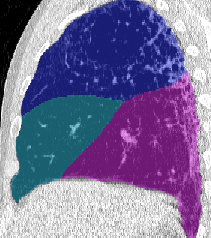

Lobar Segmentation

Lobar segmentation results for the proposed method and PTK are shown in Figure 5 for right lungs and Figure 6 for left lungs. For each image in the COVID-19 dataset (133 images in total), the lobar segmentation result was used to extract the amount of poor aeration () and consolidation () in each lobe. Common phenotypes of COVID-19 affected lungs were identified by hierarchical clustering over the fraction of poorly aerated and consolidated tissue in each lobe. Dendrographic analysis in Figure 7 reveals four primary clusters of patients that were identified by the hierarchical clustering: (a) mild loss of aeration primarily in the two lower lobes without consolidation; (b) moderate loss of aeration focused in the two lower lobes with or without consolidation in lower lobes; (c) severe loss of aeration throughout all lobes with or without consolidation; and (d) severe loss of aeration and consolidation throughout all lobes.

| CT Image | PTK | Proposed |